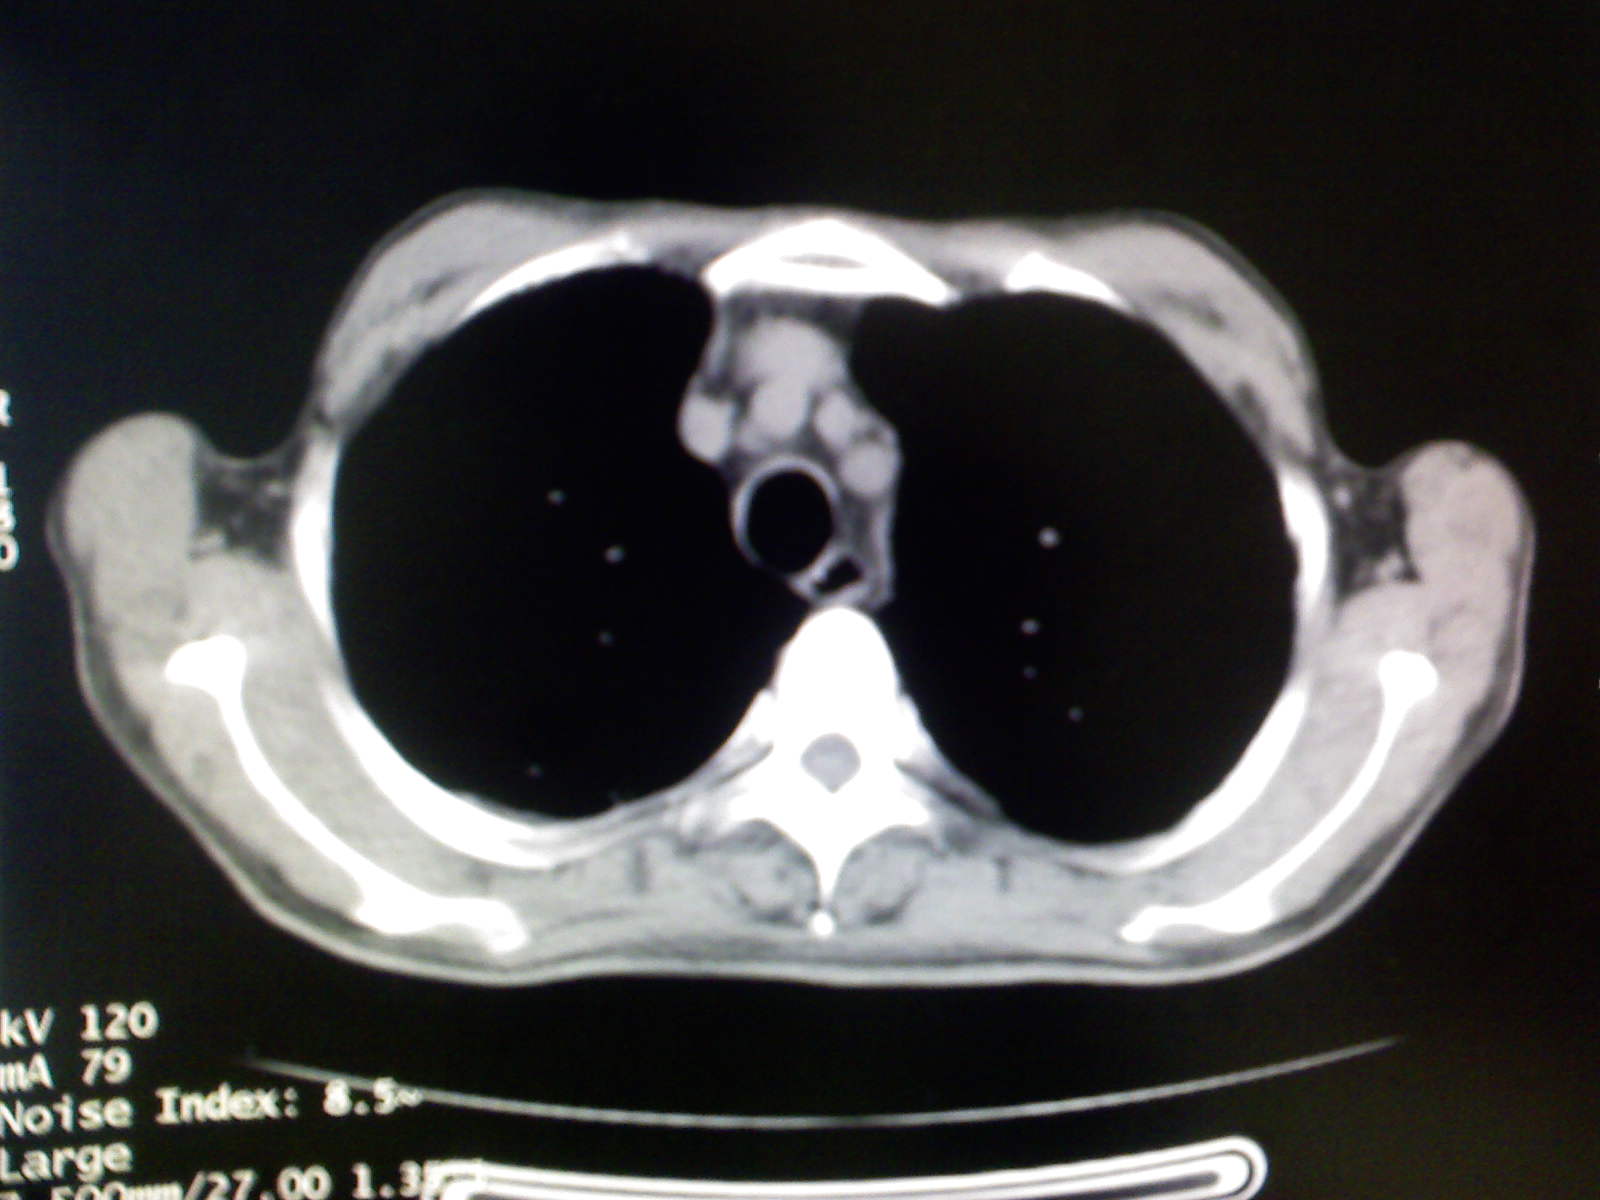

以下是引用卜一在2009-4-11 15:50:00的发言:[br]双肺继发性肺结核伴空洞形成,不排除合并霉菌感染!(病灶呈多形态 多特征 散在分布)。另:合并支气管扩张征伴感染!

以下是引用康鹏在2009-4-11 16:30:00的发言:[br]双肺继发性肺结核伴空洞形成合并感染[br]支气管扩张合并感染